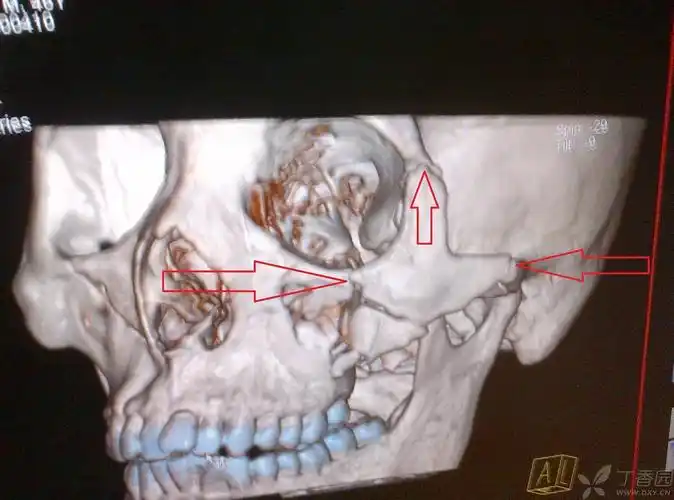

【病例讨论】上颌骨骨折何以引起张口受限 [病例帖]

【急诊】颧骨骨折,上颌骨骨折ct表现

上颌骨骨折

上颌骨骨折 [病例帖]

正颌手术# le fort ii型骨折:又称上颌骨.